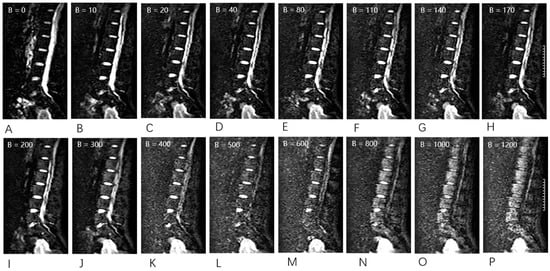

2.4. MR Examination

2.5. Image Analysis